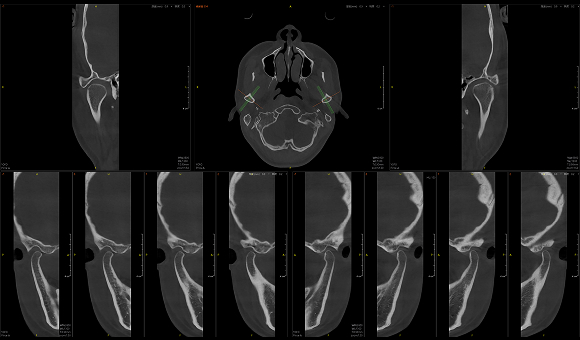

• 3D TMJ视图

3D TMJ视图